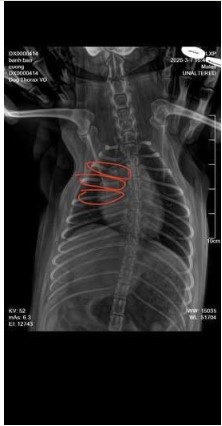

‼️😡Đà Nẵng: Thanh njên ng Trung Quốc🦵 🐕 đang gây bucxuc nhất Mxh Việt Nam 😡 downtik 9 Tháng 3, 2026 Chưa phân loại Thanh niên TQ đá 1 chú chó gãy 3 cái xương sườn https://downtik.info/wp-content/uploads/2026/03/jZ8msGFJ1.mp4